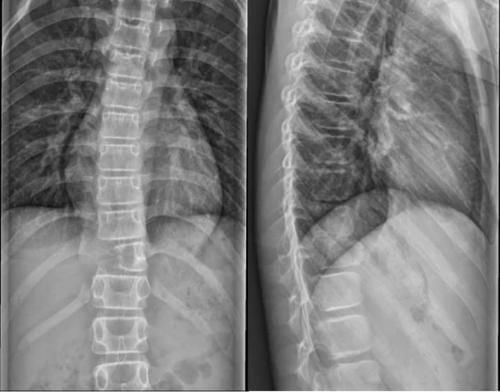

文章插图